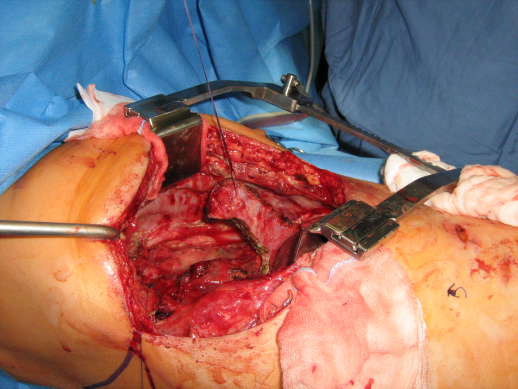

Gelegentlich sind aber die gängigen Muskelschwenklappen sind verwendbar, da beispielsweise bei der Erst-Operation (Mamma-Ablatio) oder nach einem Rezidiveingriff die entsprechenden Muskeln zerstört oder durch eine Kachexie unbrauchbar wurden. Als Alternativverfahren kommt ein Mehrstufen-Konzept zum Einsatz. Nach „en bloc-Resektion“ des Tumors (siehe Abbildung 7 [Abb. 7]) einschließlich der entsprechenden Sicherheitsabstände (Schritt 1) wird die knöcherne Thoraxwand bei uns bevorzugt durch Goretex (Goretex Dualmesh®) wieder rekonstruiert (Abbildung 9 [Abb. 9]) (Schritt 2). Andere Materialien (z.B. Vicryl-Netz®) werden nur bei Abszessen oder einem Empyem verwendet. Das Goretex hat für die Brustwandrekonstruktion entscheidende Vorteile. Durch seine Elastizität („Trabekelstruktur“ des Goretex Dualmesh®) wird die „normale“ Atmungsphysiologie wieder hergestellt. Im Gegensatz dazu ist ein Marlexnetz® starr und unelastisch und zeigt eine beträchtliche Schrumpfungstendenz. Außerdem verklebt die Lunge nicht mit dem Goretex, so dass auch dadurch keine Beeinträchtigung der Lungenmotilität erfolgt.

Abbildung 9: Goreteximplatation in die Thoraxwand